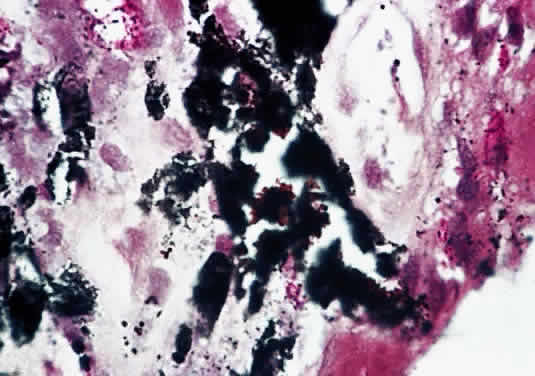

Skin biopsies from leprosy patients reveal numerous acid-fast bacilli, which may form clumps called globi. Hematoxylin and eosin staining of lepromatous skin biopsies show numerous foam cells, highly vacuolated macrophages laden with acid-fast bacilli. Skin biopsies from tuberculoid patients show few or no acid-fast bacilli, but granulomatous invasion of dermal nerves, with or without caseation, is pathognomonic. Biopsies of ocular tissues (Fig. 2) show numerous organisms inside macrophages, endothelial cells, nerves, pigment epithelium, and smooth muscle cells. There is infiltration of the conjunctiva, cornea, iris, and ciliary body with macrophages, lymphocytes, and plasma cells. Miliary lepromata are seen in iris pearls and around corneal nerves.8

Fig. 2. Light micrograph of a biopsy of an iris granuloma in a patient with leprosy. There are numerous rod-shaped bacteria consistent with M. leprae. There are multiple pigment granules with the iris stroma (Fite's stain, × 315). (Trucksis M, Baker AS: Tuberculosis and leprosy. In Albert DM, Jakobiec FA, [eds]: Principles and Practice of Ophthalmology. Philadelphia, WB Saunders, 1996.)